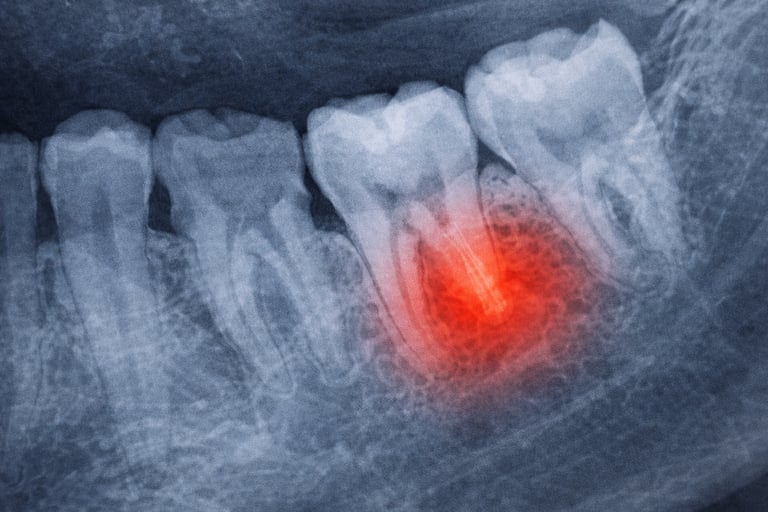

Dental emergencies can happen when you least expect them. Severe tooth pain, a broken tooth, or a dental infection can quickly become overwhelming and should be treated as soon as possible. At The Dentist Office, we provide same-day emergency dental care in Greenville, SC to relieve pain, treat urgent problems, and protect your long-term oral health.

A dental emergency is any situation involving your teeth or gums that requires immediate attention to relieve pain, stop bleeding, or prevent further damage.

Dental abscess or infection

Severe tooth pain is often caused by infection, decay, or damage inside the tooth. We diagnost the cause and provide appropiate treatment to eliminate pain.

Root Canal Therapy

If the inner portion of the tooth becomes infected, a root canal may be necessary to remove the infection and save the tooth

Treatment for Dental Infections

Dental abscesses can be serious and should be treated quickly. Our team can relieve pressure, remove infection, and protect surrounding teeth.